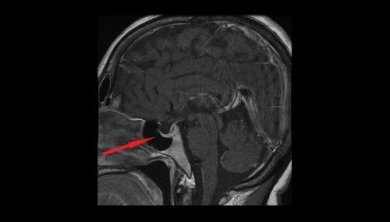

Die wichtigsten Untersuchungen, die es ermöglichen, die Diagnose zu bestätigen, sind die Sichtfeldüberprüfung sowie eine Magnetresonanz und eine Computertomographie, um Bilder vom Kopf zu machen.

- Chirurgische Entfernung des Hypophysenadenoms: Meist erfolgt der Zugang transnasal und transspenoidal, um den Tumor operativ zu entfernen. In manchen Fällen kann jedoch auch eine Kraniotomie (neurochirurgische Eröffnung des Schädels) erforderlich sein.

Eine operative Entfernung mit transnasalem Zugang erfolgt durch ein Endoskop, das in die Nase eingeführt und dann bis zur Fissura orbitalis superior geführt wird. Diese Öffnung wird erweitert, um bis zur Sella turcica (in der mittleren Schädelgrube) vorzudringen und danach den Tumor zu entfernen.